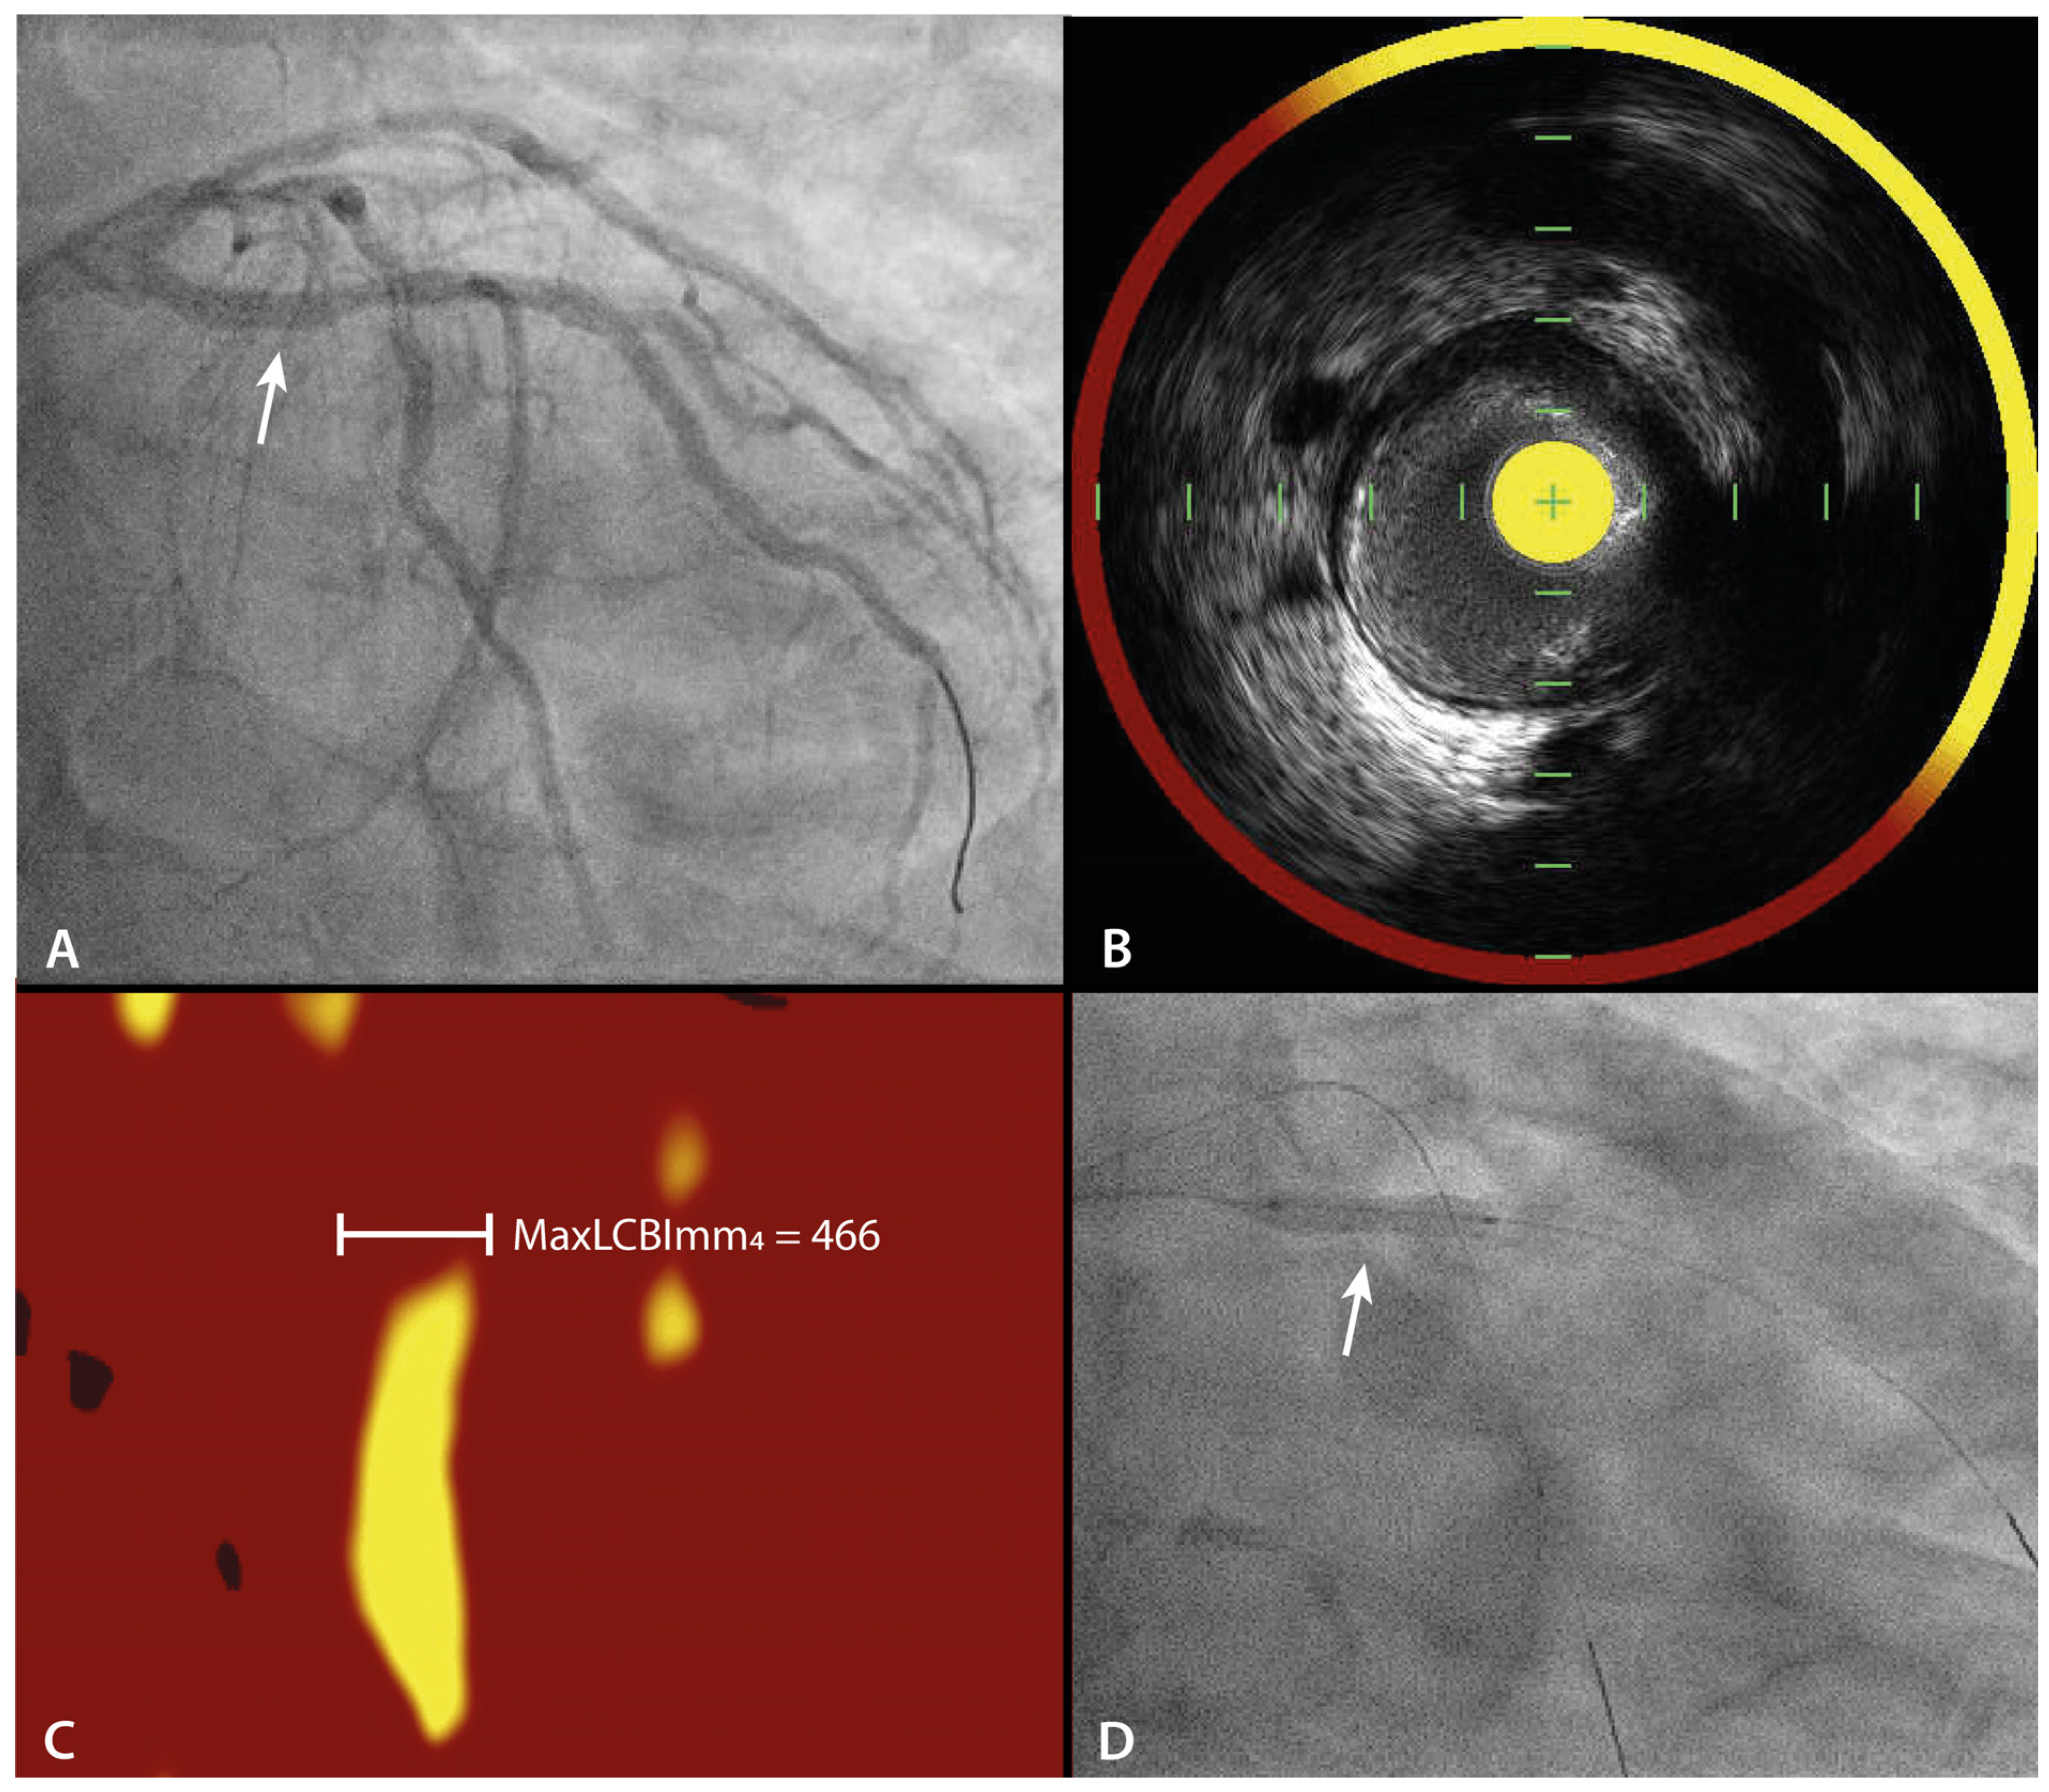

| Change in maxLCBImm4 between baseline and 9 months follow-upin PE-DCB treated LRPs. |